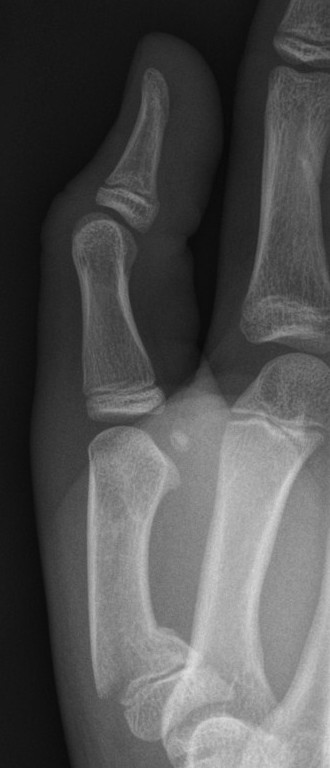

- Thumb ulnar collateral ligament injury (Gamekeeper’s thumb) is caused by hyper-abduction of the thumb.

- Assess for rotational deformity by asking the patient to make a fist. Look for “scissoring” or crossing over of the fingers.

- Assess for ulnar collateral ligament injury (Gamekeeper’s Thumb) by palpating for tenderness on the ulnar side at the base of the proximal phalanx and looking for pain / laxity on abduction of the thumb.

Suspected ulnar collateral ligament injury (Gamekeeper’s Thumb)

- Thumb spica cast and follow up with Plastic Surgery clinic in 1-2 days.